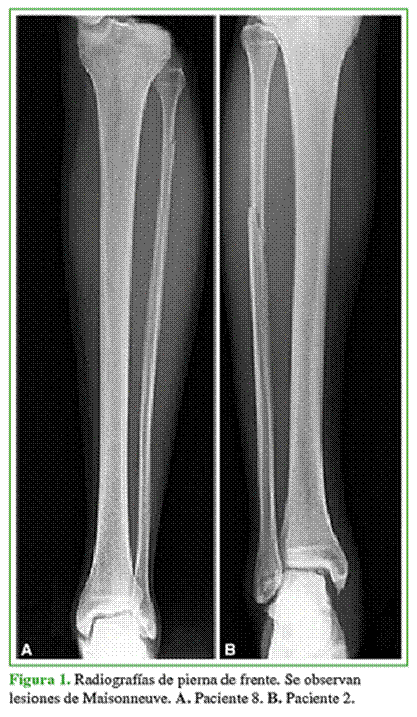

Se evaluó el registro de los pacientes con FM aguda (<6 semanas), diagnosticados con radiografía de pierna de frente y de perfil (Figura 1), tratados mediante reducción bajo visualización directa artroscópica y fijación interna percutánea, entre mayo de 2013 y enero de 2019.